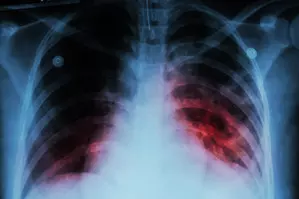

Aizawl, May 3 At least 108 people died of tuberculosis in Mizoram in 2023, state Health Department officials said on Thursday.

A senior Health Department official said that blood samples of 17,432 people suspected to be infected with TB were tested from January to December last year, of which 2,272 people tested positive for the infectious disease.

The official said that of the 2,272 TB patients, 164 were diagnosed with Multi-Drug Resistant Tuberculosis (MDR-TB) and 86 per cent of the infected patients have been successfully treated while 108 people died.